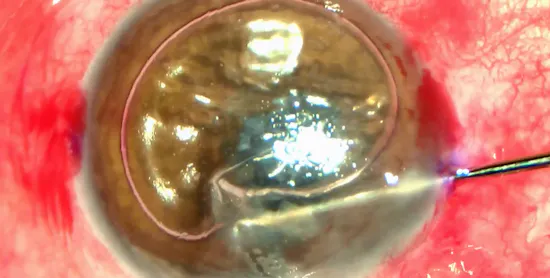

Cataract